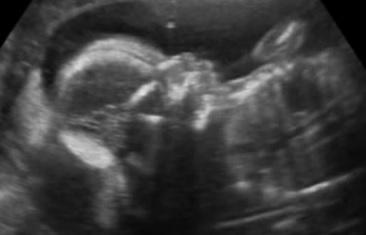

УЗИ в Арт Мед 21 неделя

УЗИ, КТГ, доплерВот наконец то настал этот долгожданный день и мы сделали Узи в Арт Мед у специалиста эксперт класса Мазырко М. Все у нас хорошо. Сделали несколько снимочков в 2D и 3D. И самое долгожданное событие - у нас будет принцесса. Можно имя подбирать и вещички прикупать!!!

Узистка начала осмотр с головы и когда спустилась ниже и начала объяснять, что вот мол бедренная кость я четко поняла, что это девочкаи начала улыбаться.Когда она промолвила, что это у нас девочка я уже в этом не сомневалась - так четко было видно.